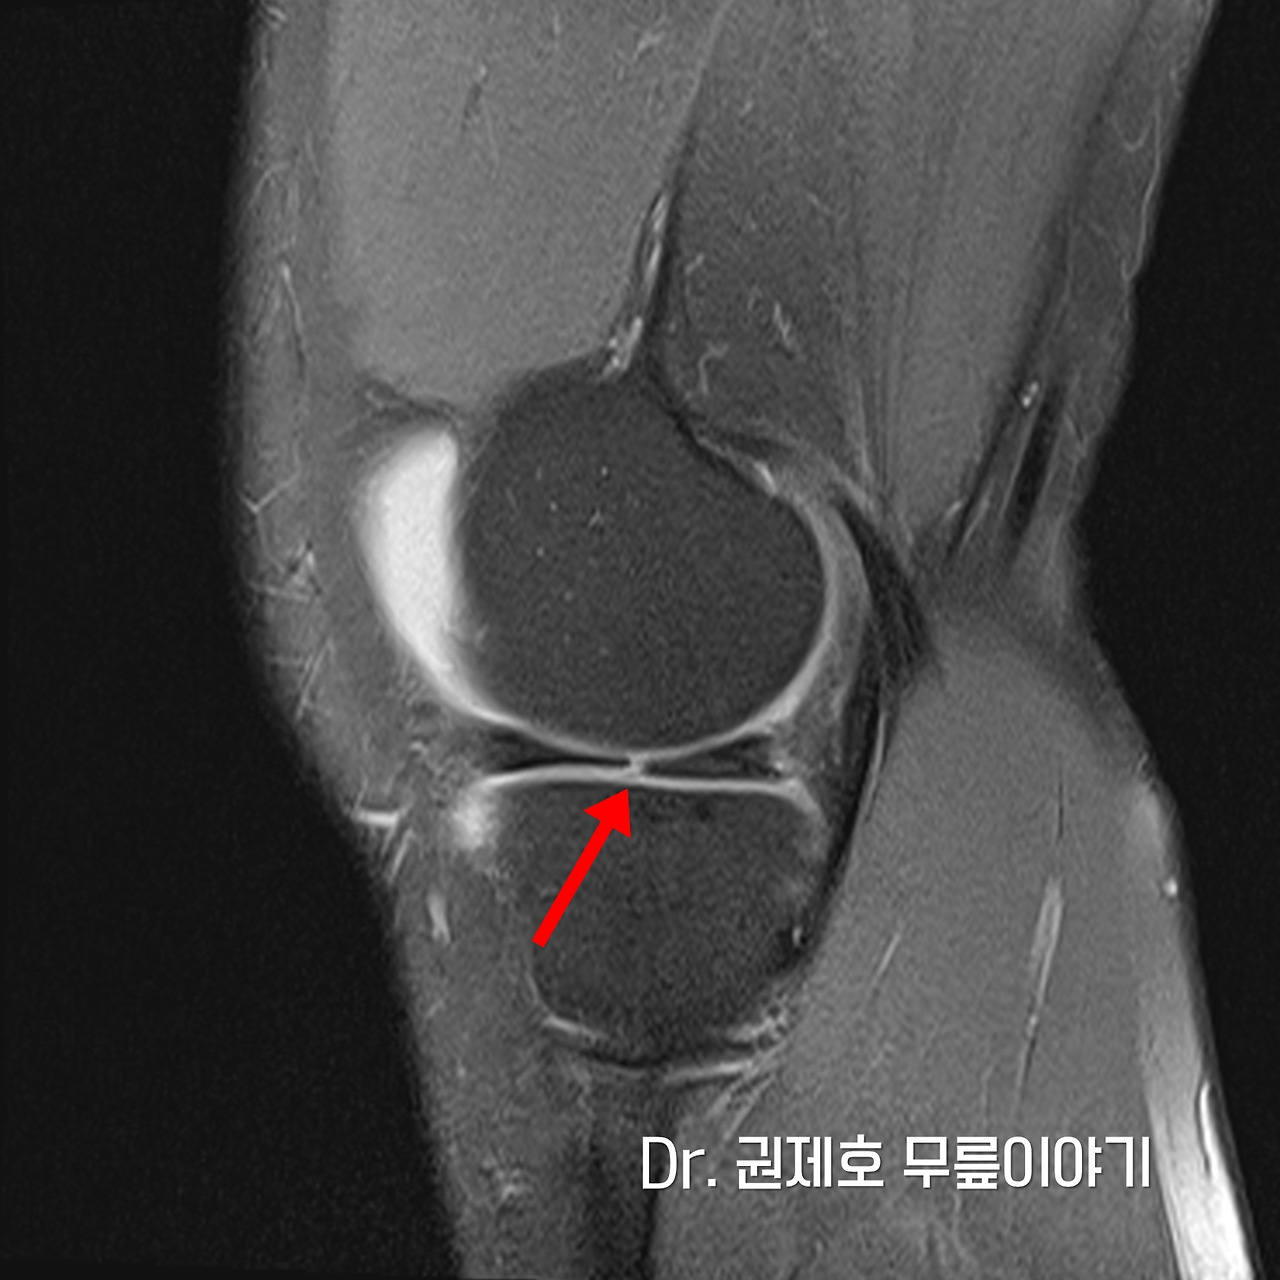

무릎 MRI 검사를 통해 무릎 속에 구조물들 중에서 어떤 것에 문제가 있는지 확인하게 되는데, 검사 결과 무릎연골판이 방사형파열이 있음을 확인하였다.